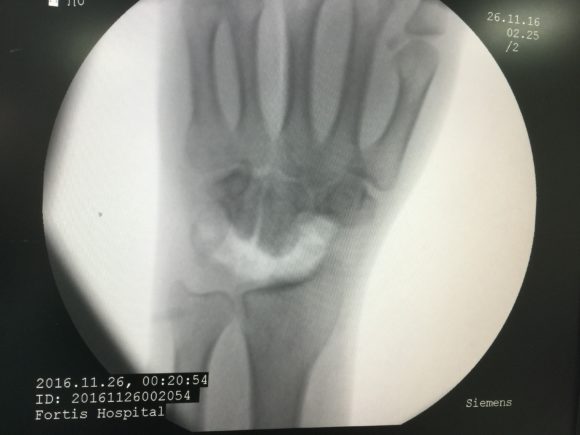

Arthroscopy utilizes a small camera and microinstruments that enable your surgeon to see inside the joint without making large incisions into the muscle and tissue. Similar to arthroscopy of bigger joints like Knee and Shoulder, Wrist arthroscopy is used to diagnose and treat problems inside the wrist joint. The instruments inserted in the wrist are between 2 to 3 mm in diameter.

• Wrist fractures. Small fragments of bone may stay within the joint after a bone breaks (fractures). Wrist arthroscopy can remove these fragments, align the broken pieces of bone, and stabilize them